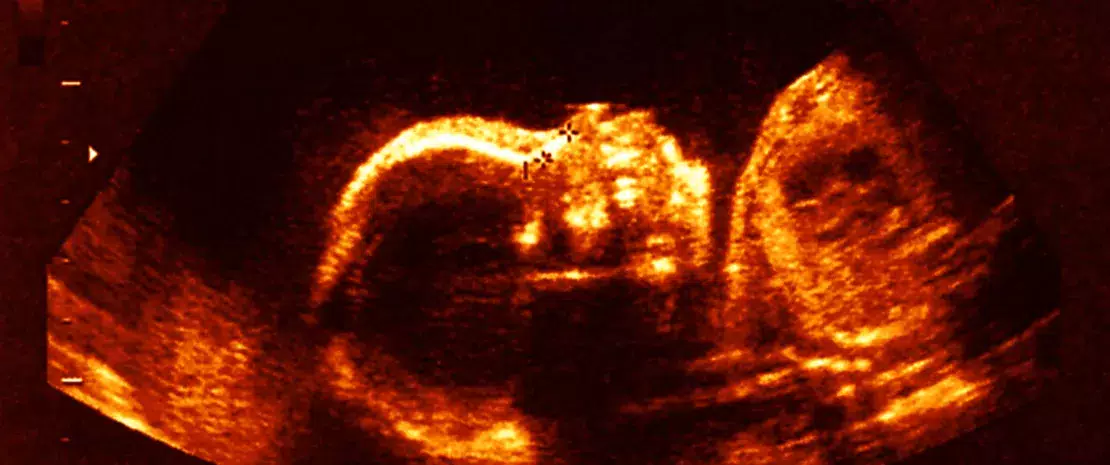

C’est immédiatement après la naissance que débute la maturation du microbiote intestinal. Cette maturation se poursuit au cours des premières années, en parallèle de celle du système immunitaire. Or, la mise en place de cette flore intestinale et le développement immunitaire sont impliqués dans les allergies, avec, pour chacun d’entre eux, le soupçon de facteurs d'influence prénataux. Le méconium, première selle du nourrisson, contient les métabolites produit in utero. Reflet des influences périnatales, puisqu’il se forme dès la 16ème semaine de gestation, il représente aussi le substrat de départ pour le microbiote initial de l’enfant. D’où cette étude tentant de relier signatures métaboliques du méconium, maturation du microbiote et développement du système immunitaire.

Pour comprendre l’origine de cette différence de maturation, les chercheurs ont remonté le temps et analysé, dans un sous-groupe de 100 enfants, des échantillons de méconium. Les chercheurs y observent une moindre diversité bactérienne chez les futurs atopiques. La diversité métabolique est également réduite, avec moins de molécules associées au métabolisme des acides aminés, des vitamines et des hormones. De quoi suggérer que des différences influençant le développement du microbiote et, en fin de compte, le développement immunitaire, existeraient dès la naissance. Ainsi, l'atopie à 1 an serait associée à la fois à un méconium métaboliquement moins riche à la naissance et à une réduction de la diversité et de la maturation du microbiote au début de la vie. Un possible mécanisme d’action est suggéré : les métabolites du méconium, miroir des expositions prénatales, seraient métabolisés et fermentés par les bactéries. Ainsi, le microbiote intestinal de début de vie, et in fine le développement immunitaire, seraient impactés par la vie in utero.